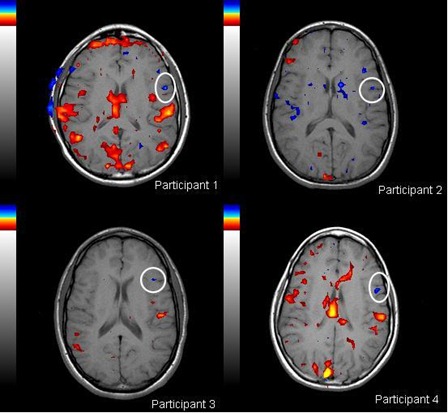

risonanza magnetica funzionale autismo